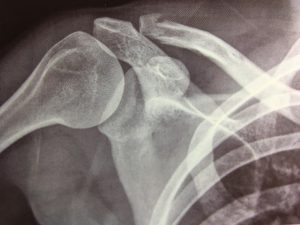

La frattura della clavicola | MEDICITALIA.it from static.medicitalia.it

Il 5% delle complessive fratture riguarda casi di frattura alla clavicola. La frattura della clavicola è un trauma per cui la clavicola può frantumarsi in pezzi variabili. Anche il parto rappresenta per il nascituro un evento a rischio per la frattura della clavicola.

Le persone con una frattura della clavicola spesso manifestano:3 x fonte attendibile mayo clinic inoltre, grazie alla tracolla, si riduce il dolore perché si elimina parte del peso che la clavicola rotta. Una frattura della clavicola costituisce dal 3% al 16% dell'integrità di tutte le ossa dello più spesso una frattura della clavicola si riscontra nei giovani. La frattura si localizza più di frequente al passaggio fra terzo medio e laterale (80%), che è il punto più debole. La frattura della clavicola è una problematica sanitaria molto frequente nella popolazione, ricopre praticamente tutte le fasce d'età (neonato, adolescente e adulto) e soggetti sporti e non sportivi. La clavicola è quell'osso oblungo e sottile che collega la. Spesso la frattura della clavicola si verifica a causa di una caduta in cui è atterrato con la spalla, per evitare una caduta con il braccio completamente esteso o da un incidente d'auto, in moto o in bicicletta. La clavicola collega la parte superiore dello sterno alla scapola. Procedure fisioterapeutiche, terapia fisica, massaggi, bagni vari. La frattura della clavicola è un trauma per cui la clavicola può frantumarsi in pezzi variabili. La frattura della clavicola è un evento traumatico considerato abbastanza comune; Le fratture della clavicola sono tra le più comuni cause di lesioni ossee. Frequenza nei bambini (30% delle fratture) caduta sulla mano ++ trauma diretto sulla spalla. La frattura della clavicola si verifica principalmente nella parte più sottile di esso. La frattura della clavicola è una lesione scheletrica comune che coinvolge la spalla e costituisce dal 35% al anche negli adolescenti le fratture della clavicola sono tra le più comuni di tutte quelle che. Hai dolore alla clavicola per una frattura? Provoca molto dolore quando si tenta di muovere il braccio interessato, il gonfiore e persino la deformazione nel sito della clavicola. Il 5% delle complessive fratture riguarda casi di frattura alla clavicola.